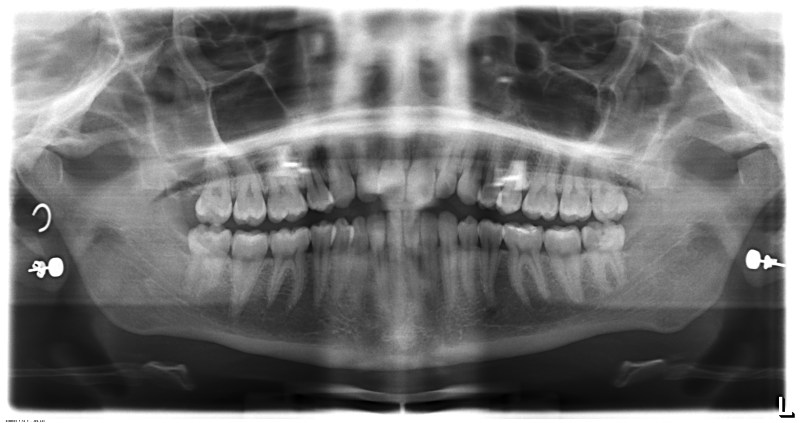

But this week, having decided I had to at least get ONE thing ticked off my to-do list, I walked into a Wudaokou dentist, and just happened to catch an English-speaking assistant before she left work at 9.30pm. So they X-Rayed me, had a prod about to discern where the pain was coming from and then gave me an appointment.